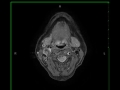

Glomus Vagale Paraganglioma, right

22-year-old male presented for evaluation of hoarseness. Arising along the posteromedial aspect of the right carotid sheath, between the right carotid arterial system superior to the bifurcation and the right internal jugular vein, there is a circumscribed, T1-isointense mass with avid, heterogeneous, postcontrast enhancement and mild diffusion restriction. The lesion was hyperintense on the T2/STIR-weighted images, and several prominent flow voids were identified. The lesion splays the carotid and jugular vessels. Differential includes right glomus vagale paraganglioma, vagal schwannoma, neurofibroma and carotid space meningioma. This is a right glomus vagale paraganglioma. Glomus vagale are avidly enhancing masses in nasopharyngeal carotid space arising approximately 2 cm below the jugular foramen. Multiple lesions can be seen with hereditary paraganglioma and pheochromocytoma syndrome, multiple endocrine neoplasia-2, and von Hippel-Lindau syndrome.